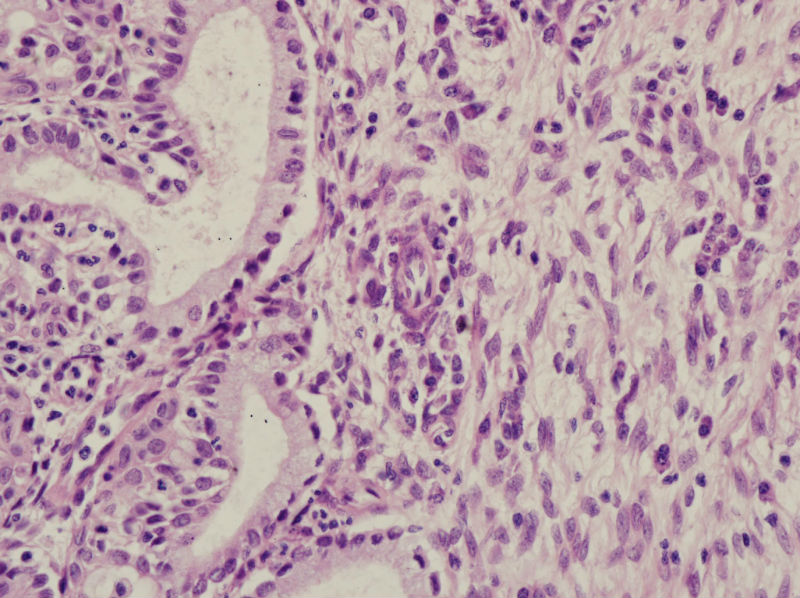

45岁,宫颈息肉?请老师指教

图1